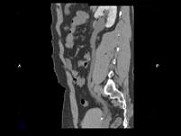

男,29岁,反复发作血尿1年余,CT如图所示,下列说法正确的是()

A.左侧肾盂扩张积水

B.左侧输尿管扩张

C.左侧输尿管末端,膀胱入口处可见高密度影

D.左输尿管结石

E.膀胱结石

[多选题]男,29岁,反复发作血尿1年余,CT如图所示,下列说法正确的是()A.左侧肾盂扩张积水B.左侧输尿管扩张C.左侧输尿管末端,膀胱入口处可见高密度影D.